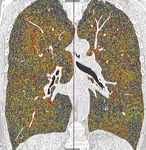

Fig. 3. Homogeneous emphysema with predomi-

nance on the right side (coronal densitometry); a uni-

lateral procedure is suggested.                            Select patients with homogenous emphy-